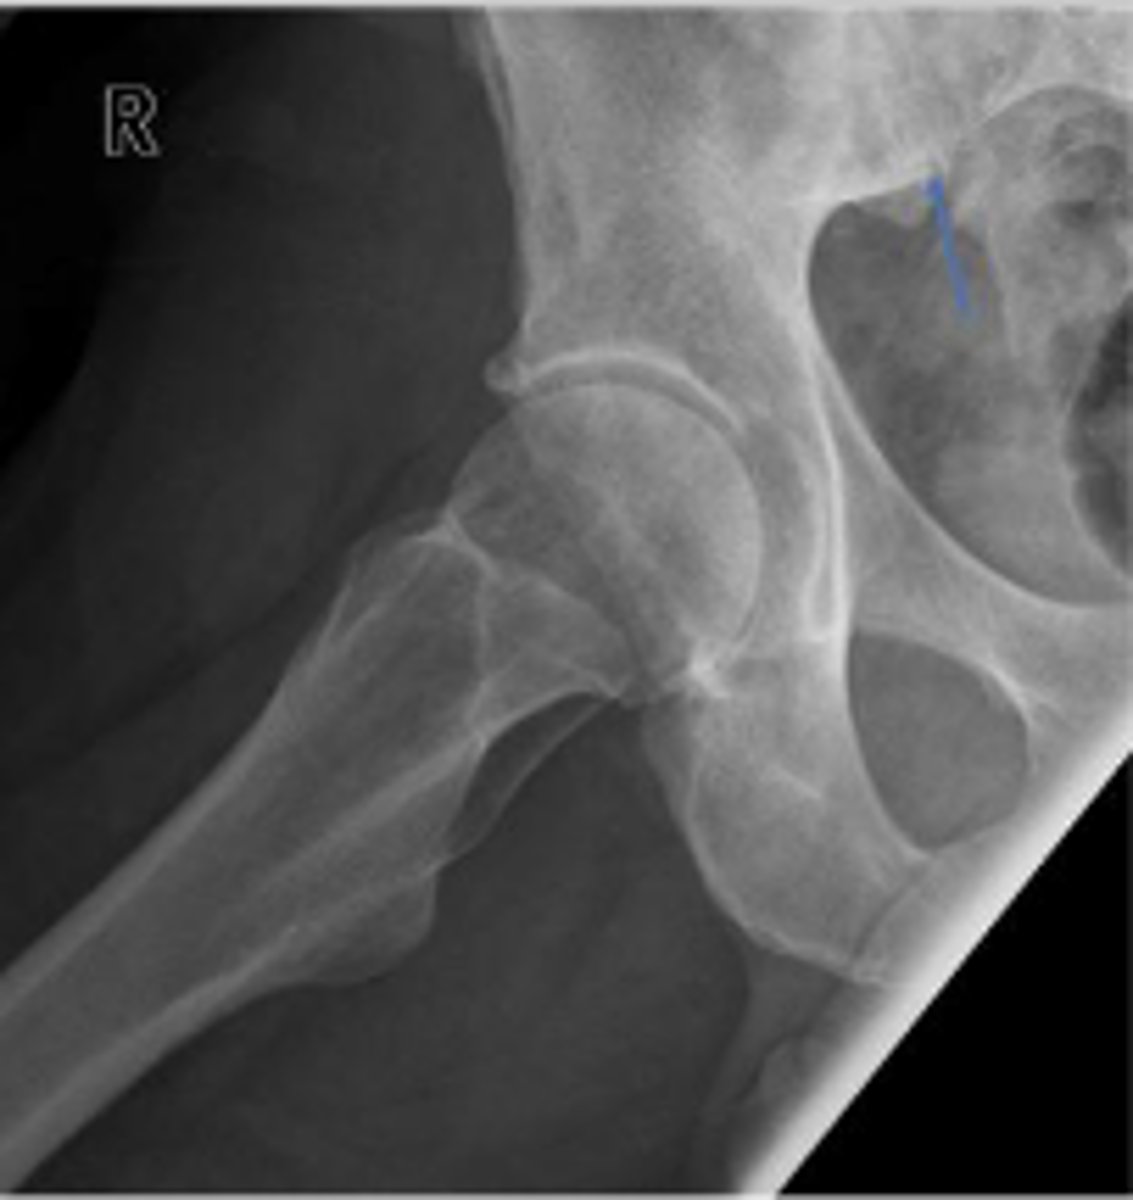

Right AP hip

What is the name of the radiographic view?

Posterior rim of the right acetabulum

What are the arrows pointing to?

Anterior rim of the right acetabulum

Posterior rim of the left acetabulum